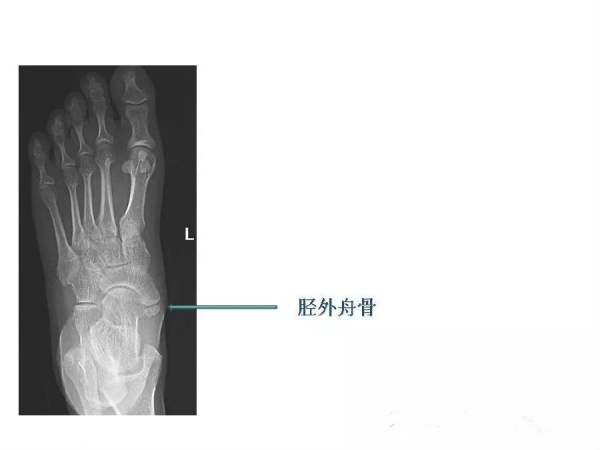

作者:金牛区人民医院CT室 严嘉军